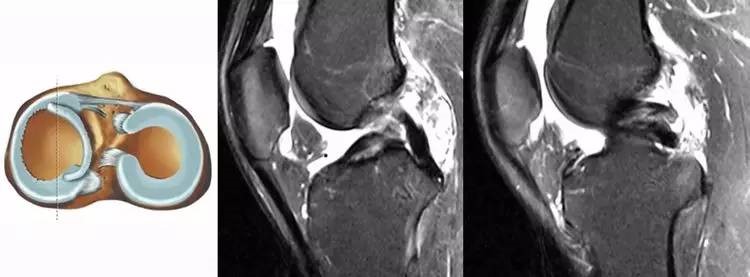

2.方向异常(ACL 下垂征):有较完整的韧带低信号,但方向异常,呈下垂状。一般见于股骨附着部的陈旧损伤,损伤的ACL下垂并粘附在PCL上。